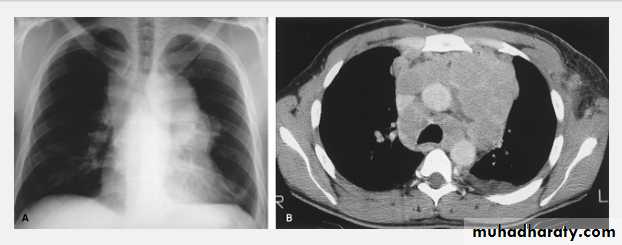

Thymoma.

A chest x-ray (A) reveals an unusual contour over the left hilum (arrows). That the hilum is not obscured (no silhouette sign) indicates that the mass must either be in front of or behind the hilum. A computed tomography scan (B) reveals a soft tissue mass (arrow) just to the left of the aorta. This is the most common location of a thymoma.